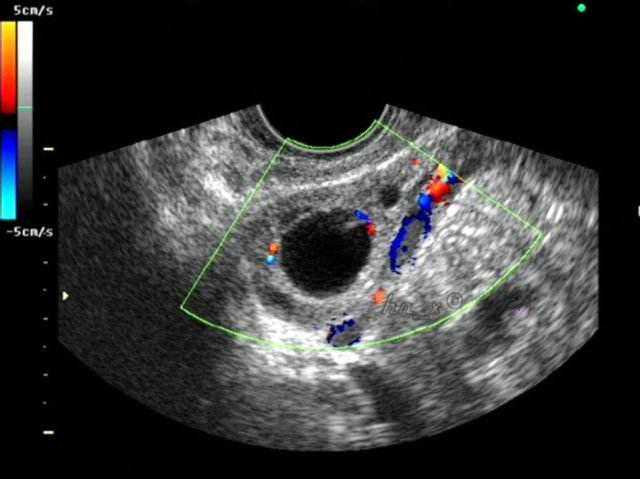

超声监测排卵:通过超声观察卵泡从发育、成熟到最后成功排出的整个过程。

如上这三种方法,小编觉得监测体温的做法效果较差,因为人体的体温本来就略有波动,且影响体温波动的因素极多,很难作为一个准确的依据。比较推荐的做法是:先用试纸测排卵,测到试纸差不多有模糊中队长的时候,再去医院用超声监测排卵,一般在卵泡长到1.8cm以上后,就说明即将发生排卵,这时候同房的成功率是最高的。

方法二、阴道超声来监测排卵

腹部超声的话,需要大量饮水,来排出气体对超声波的影响。但阴道超声就不受腹部脂肪层和肠道气体影响了。有的女性每次腹部超声都因喝水而苦恼,或者比较胖的姑娘腹部脂肪层较厚,可以采用阴道超声的做法,效果会比腹部超声效果更好些。